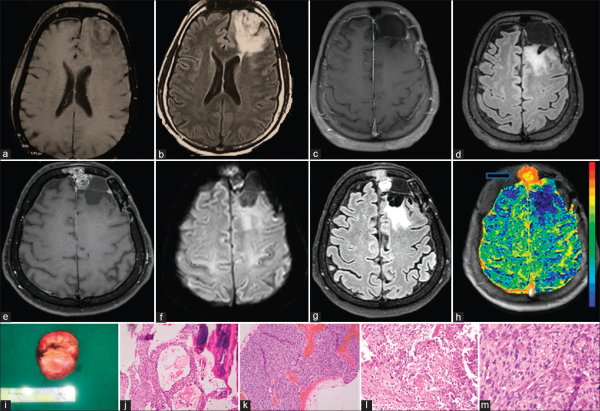

一位53岁的男士因全身性强直和阵挛性癫痫发作入院治疗。大脑的磁共振成像(MRI)显示左额叶区域有肿块,显示轻度斑块增强。术后组织病理学显示WHO II级少突胶质细胞瘤。于2012年5月11日进行的MRI检查显示,手术腔的后缘和内侧边缘有少量不增强的残留疾病。该患者开始接受强度调制放射治疗(IMRT),在47天的时间内采用每次54 Gy的剂量。放疗后,他每年接受定期的MRI随访,显示原发疾病无间隔变化。但是,在五年后,另一例无症状的患者的后续灌注MRI显示,硬膜受累左额骨的病变增强。MR灌注显示出一种高度疾病,相对脑血容量(rCBV)值显着增加。进行了广泛的病变切除,并且组织学证实它是骨肉瘤。